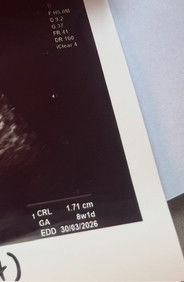

Ukuran Scan berbeza dengan LMP

saya scan masa 8 weeks tapi ukuran baby baru 6 weeks 5 days. Alhamdulillah heartbeat dah nampak. Ada yang sama macam ni tak?

sama, kalau ikut lmp dah 8w tapi scan dua hari lepas baru 6w6d. Alhamdulillah, heartbeat pun dah nampak. semoga yang baik2 saja utk baby kita